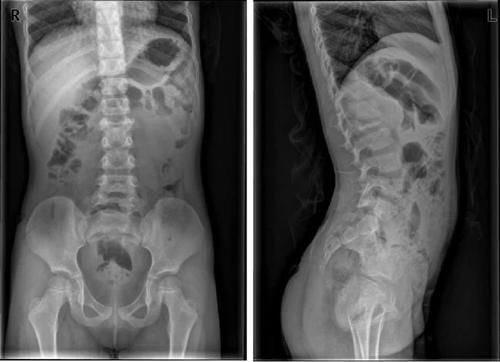

Case14:M,6y;双侧髋部疼痛1月余,加重伴不能行走半月。